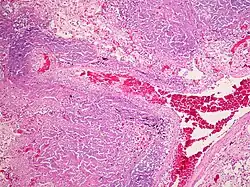

A Tuberculose miliar ou tuberculose cutânea aguda disseminada é uma classificação médica internacional para um agravamento da tuberculose por sua ampla difusão dentro do corpo humano gerando pequenas lesões na pele (de 1 a 5mm).[1]

Infecções tuberculosas generalizadas frequentemente causam alterações inespecíficas nos exames laboratoriais de rotina, podendo passar despercebidas em uma radiografia de tórax, sendo assim recomendado o exame de material obtido por punções, procedimentos cirúrgicos ou necropsias.[2]